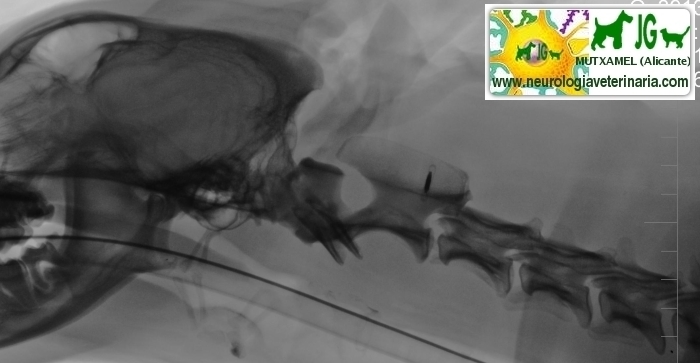

Radiografía simple (sin contrastes) | |||||||||

Radiografía digitalizada de cachorro de Siberian Husky con severo trauma craneal |